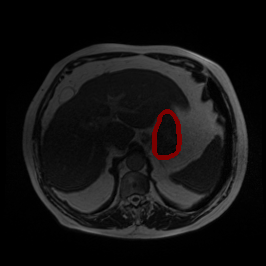

Undersampling Artifact

MRI GMAIMMbench Organ Recognition - Abdomen

Undersampling Artifact - L0 (Original)

L0

L0 (Original)

Question

This is a MRI image. Which of the following options is the most appropriate to describe the marked area?

A lung B necrotic tissue C stomach D fascia uncovered kidney parenchyma

Ground Truth: C. stomach